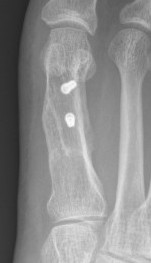

Fixation

- screws / plate / screws + plate